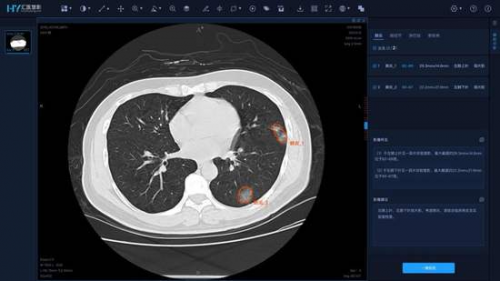

華為IdeaHub瞄準互聯網診療領域,可以同時為患者端、多地會診醫生及醫療機構輸出4K醫療影像數據,能夠讓多學科會診醫生實時通過影像病理信息進行討論,給出綜合診斷及意見,為智慧醫療帶來一次升級。

這時候,華為IdeaHub價值體現出來,通過投屏碼投屏、二維碼投屏等方式,科室醫生之間可以快速共享像病人CT、診斷報告等文件,而不同園區的醫療人員,可以同時在企業智慧屏上書寫、標注,縱向上,這方便了上下級專家與主治醫生共同制定診療方案,橫向上,這可以讓多科室專家的疑難雜癥更便利。

而華為IdeaHub云會議視頻可達到1080p云會議,共享文檔擁有4K超清分辨率,色域編解碼能實現BT.2020標準。例如在鄭大一附院的應用中,借助華為IdeaHub能夠讓醫護人員清晰看到遠端病人的醫療圖像數據,應對影像會診等專業診療情況,同時,華為IdeaHub也能支撐一些需要高清晰、高還原圖像輔助的高難度手術需求,在智慧醫療解決方案中實現更清晰化的展示助力。